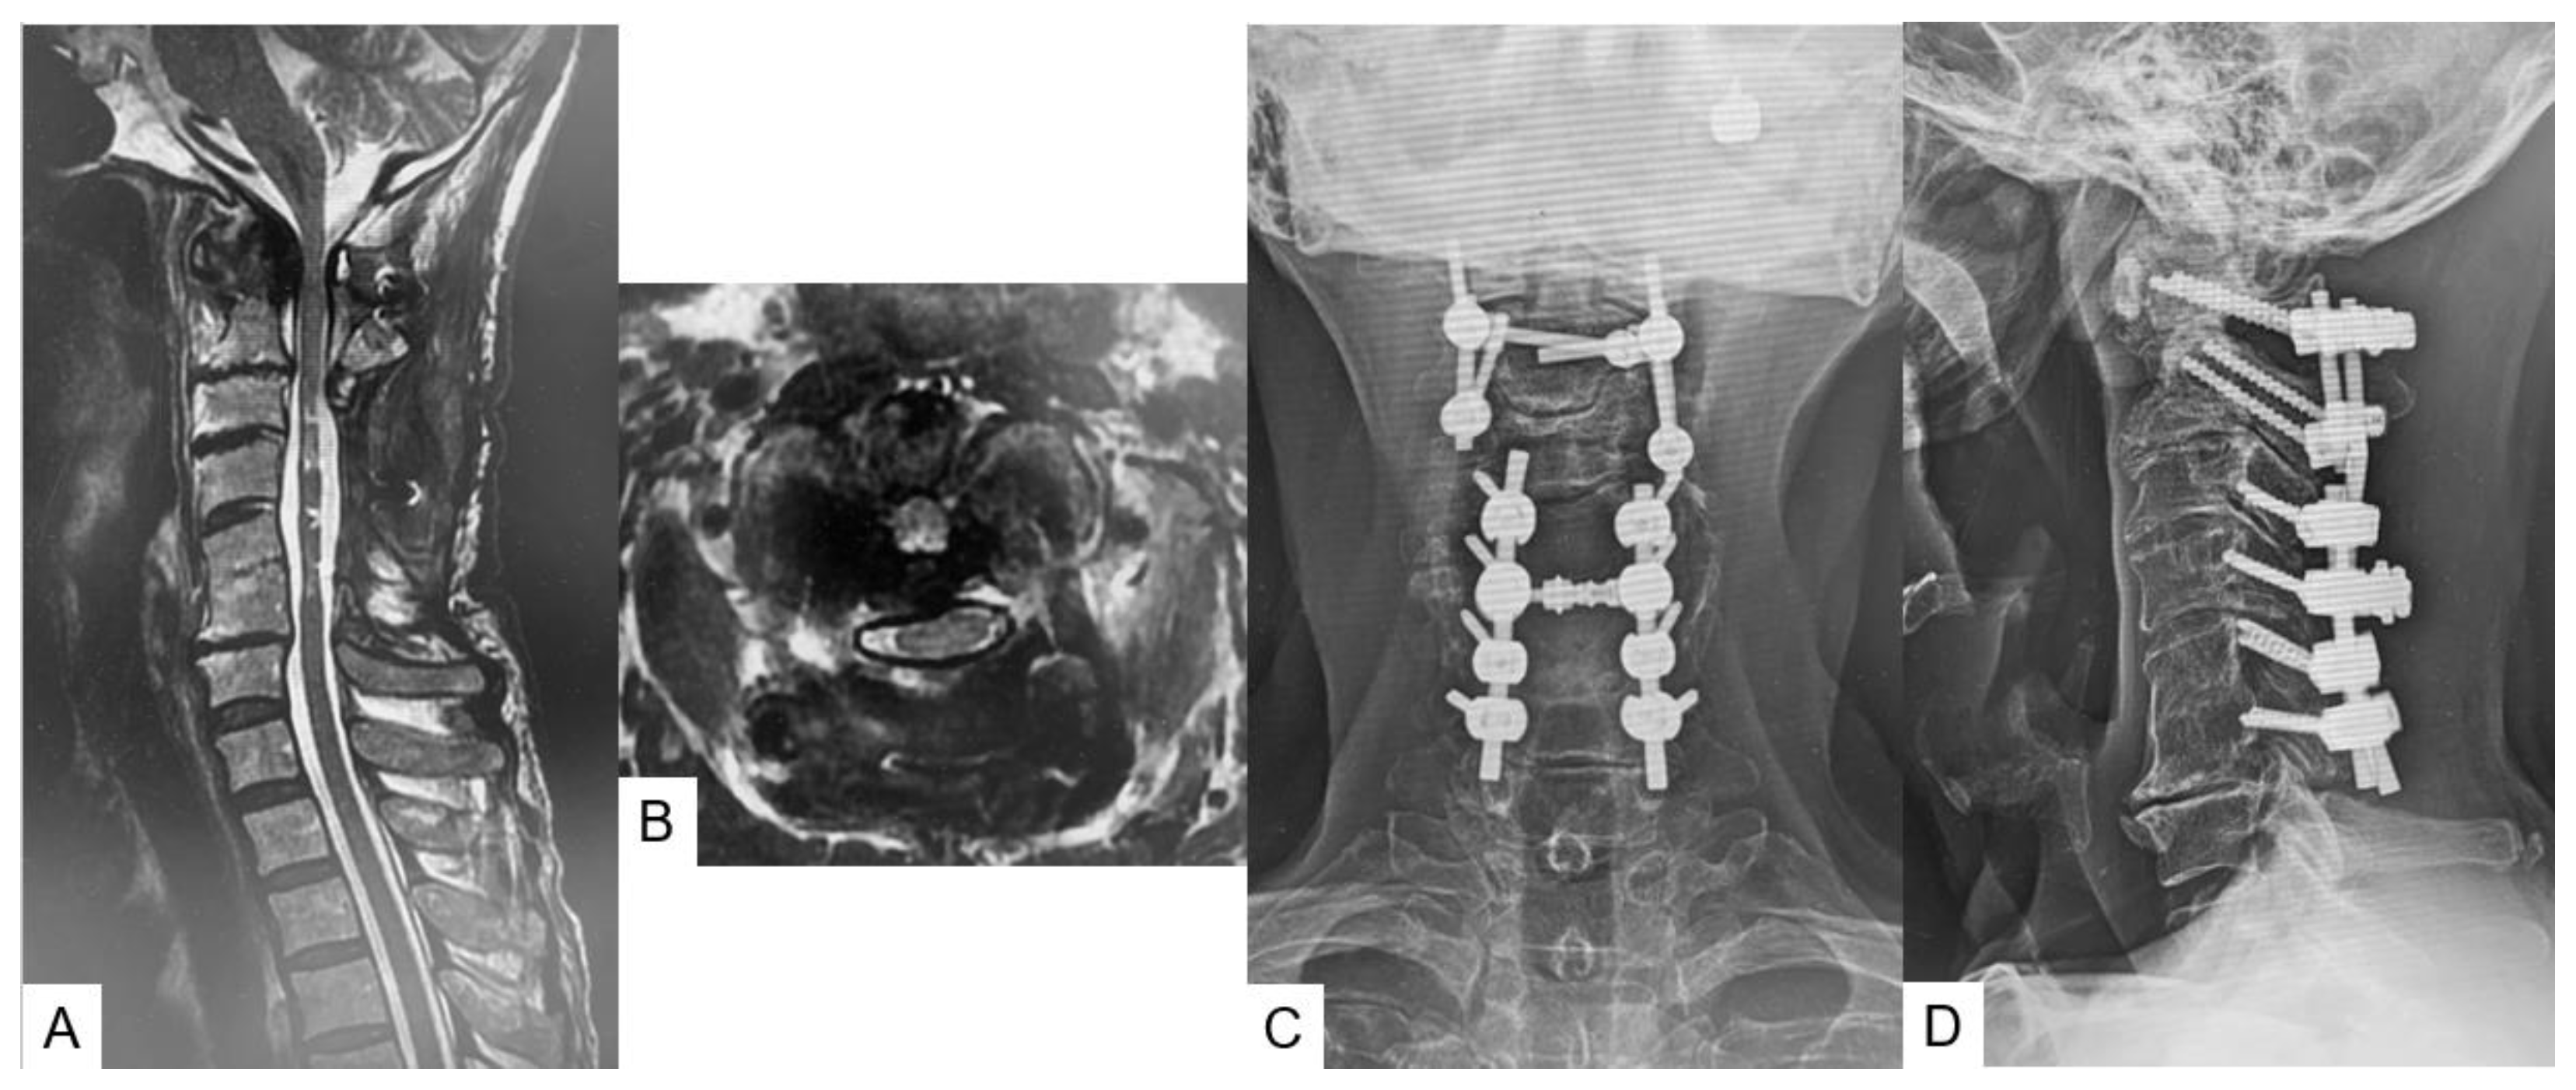

2.3. Preoperative Imaging

2.5. Postoperative Imaging

2.6. One Year Follow-Up